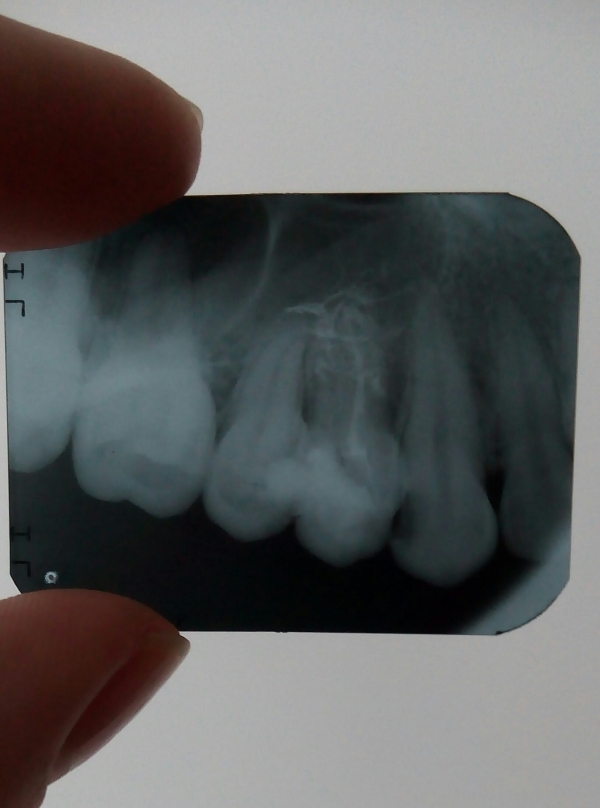

Попала к девушке со стажем работы 1 месяц. Мне удаляли нервы, но не смогли полноценно запломбировать зуб. Только один из каналов вроде запломбировали, т.к. из канала шла кровь, и они не могли её остановить. Прижигали мне там что-то по 10 раз. Поставили временную пломбу, а под нее вату. На следующий день тоже самое, на помощь молодому врачу подключилась врач со стажем. Она посверлила еще и нашла еще один канал. Опять прижигали. Шептались постоянно, я услышала фразу про две перфорации. Послали на рентген. Следующий прием только через 3 дня. К ней точно не пойду, уже нет доверия. Это была стоматология по ОМС. Пойду в платную стоматологию, может, спасут зуб.

Перфорация может быть стенки корня, стенки коронки, верхнечелюстной пазухи и т.д.

По снимку, определить о какой перфорации шептались Ваши врачи, не представляется возможным.